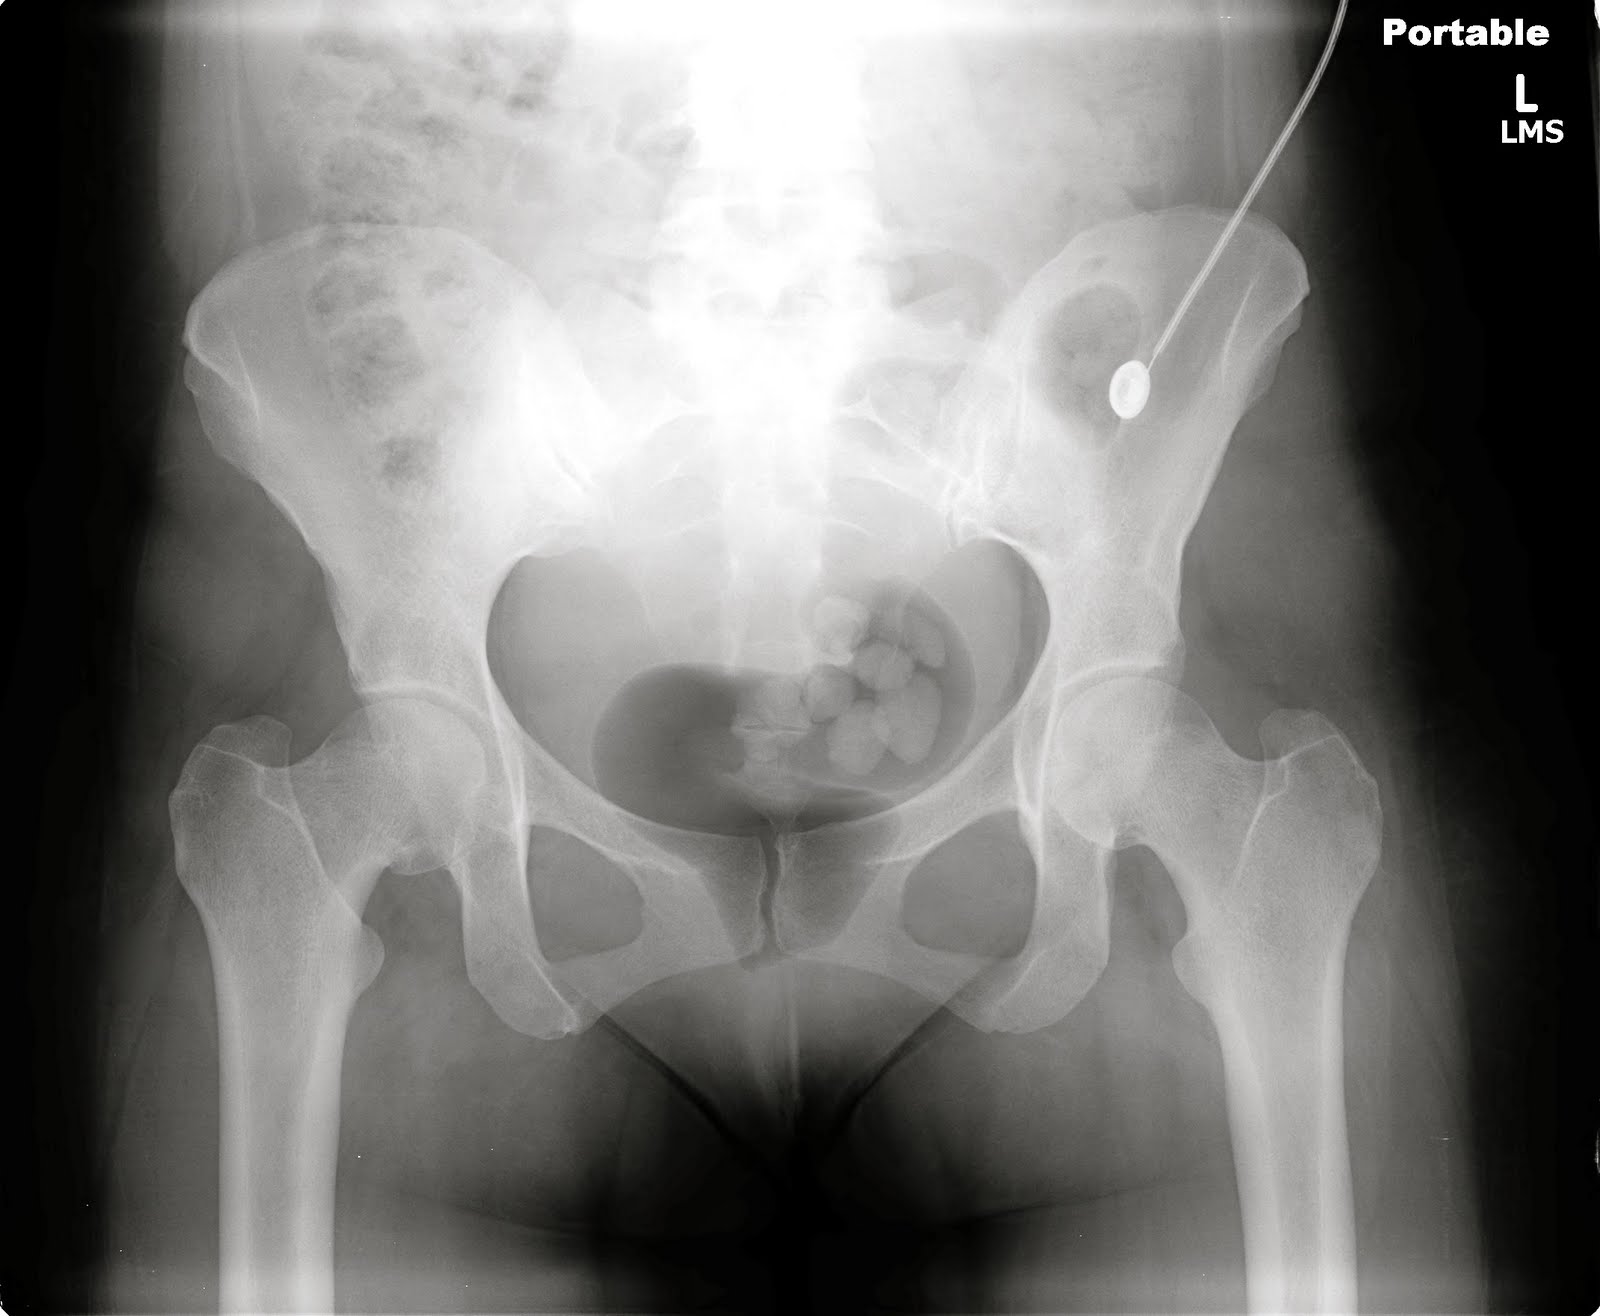

The patient was a hard working handyman who had been recently diagnosed with metastatic cancer. He had noticed a lump on his ribs a month prior, and it was discovered that lump was actually metastatic cancer to his ribs from a gastrointestinal source. He was in the ER for worsening pain. I looked through the computer to see what follow up appointments he had, and I noticed he was to be see in palliative care clinic in the next few weeks. Right then I knew his prognosis. Patients don't go to palliative care for cancer treatment, they go there so their pain can be controlled as the cancer spreads until they die. I talked to him and his wife for a bit, and could tell they still had hope of possible treatment. The past month had been a shock for them, as it would for any of us.